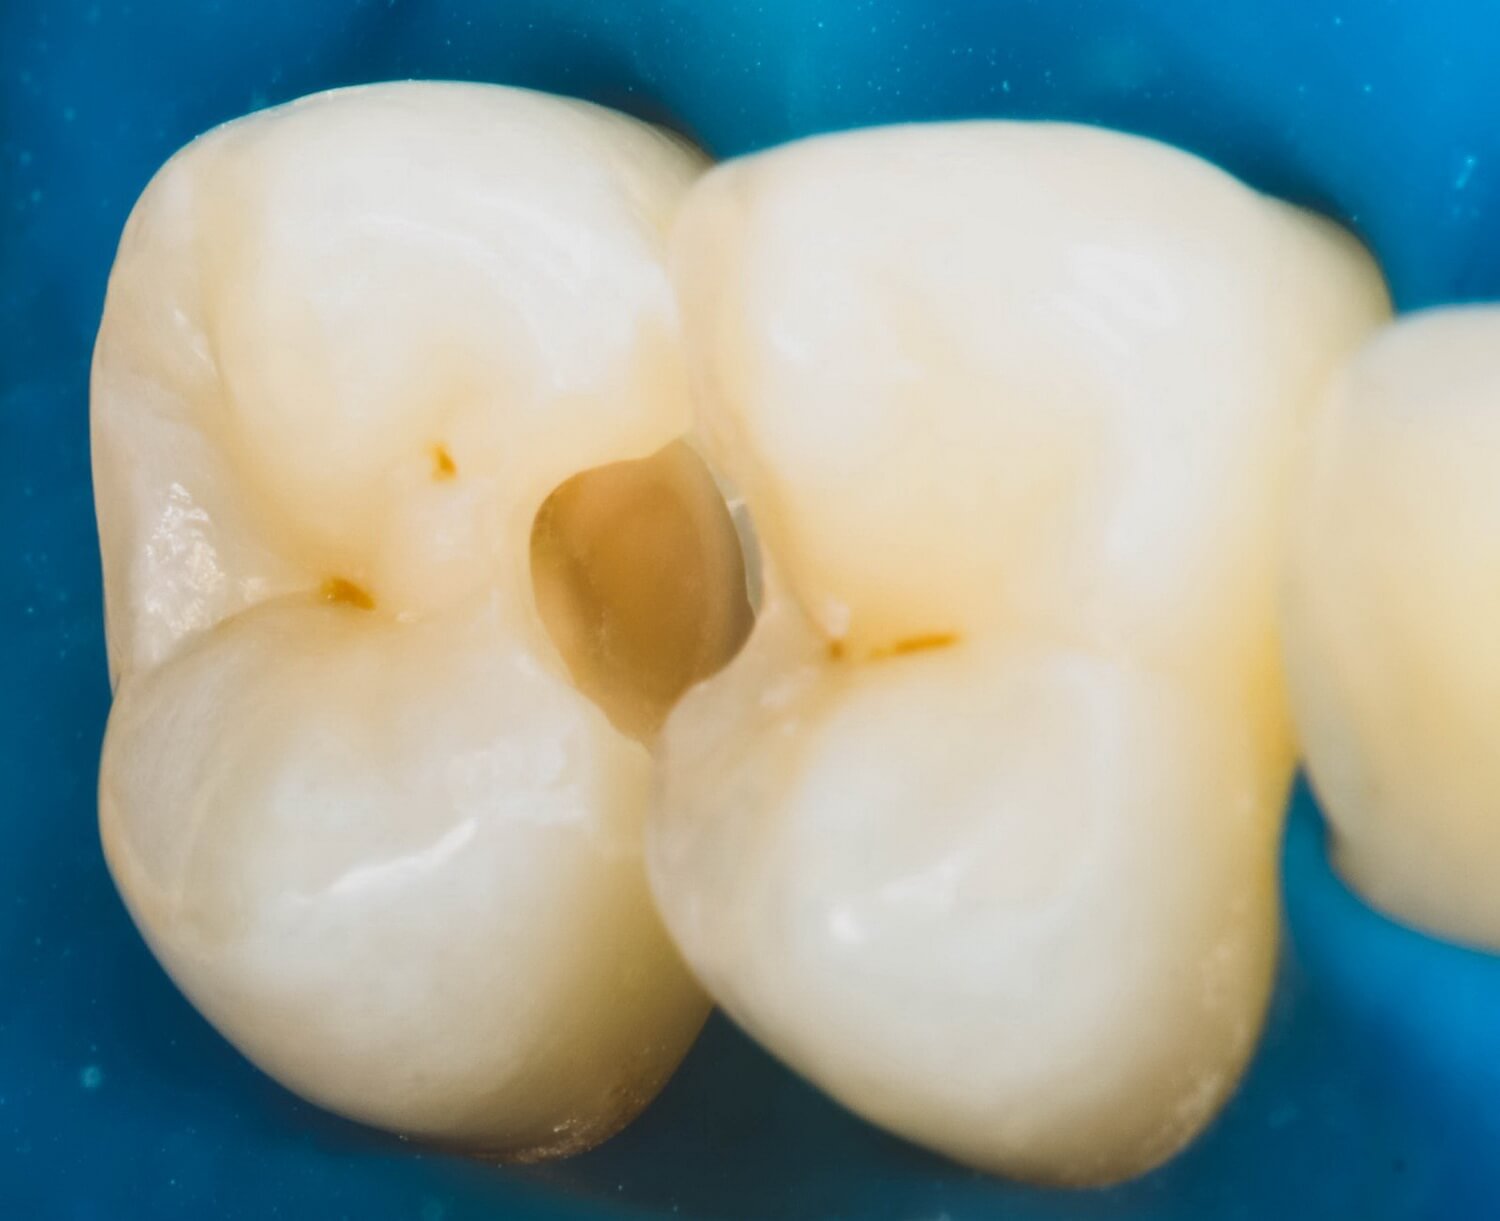

Кариозные полости мы подготовили в современной концепции «минимально-инвазивного препарирования, что возможно только с большим увеличением и освещением (рис. 3 и 4).

![]() Рис. 3. Отпрепарированная полость зуба 2.5: вид сбоку с максимальным сохранением твердых тканей на жевательной поверхности. | ![]() Рис. 4 Отпрепарированная полость зуба 2.4: вид сбоку с максимальным сохранением твердых тканей на жевательной поверхности |